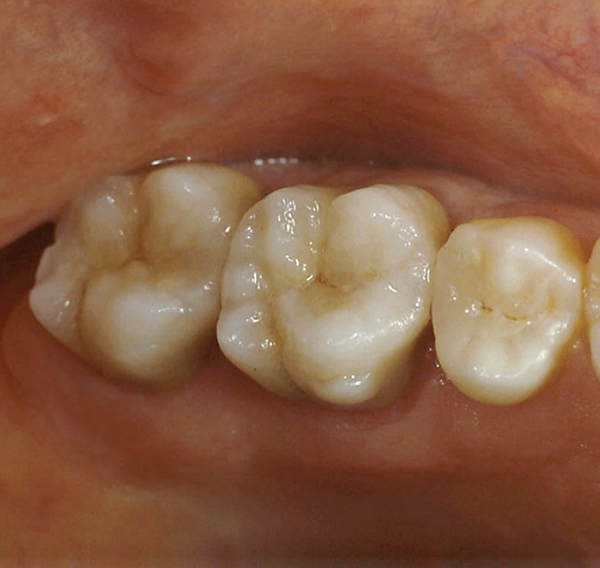

CL-IIIb high-strength 100% crystalline ceramics initially were alumina-based materials (eg, Procera®, Nobel Biocare, www.nobelbiocare.com); more recently they are zirconia-based (eg. LAVA™, 3M ESPE, www.3MESPE.com; Prettau®, Zirkonzahn, www.zirkonzahn.com). Alumina systems have proven successful for single units but are being replaced by zirconia and lithium disilicate due to the increased risk of failure in the molar region.25,26 Zirconia can also be used when significant tooth structure is missing, when high risk for flexure and stress is present, for posterior full-crown and fixed partial denture situations (Figure 13 and Figure 14), and when adhesive bonding is problematic, such as with subgingival margins.

In cases where the bond and seal cannot be maintained (ie, high-risk bonding situations, including moisture control problems, high shear and tensile stresses on bonded interfaces, and variable bonding interfaces), high-strength CL-III ceramics or metal ceramics (CL-IV, see below) are appropriate, because they can be placed using conventional cementation techniques. A concern with full-contour zirconia, however, is wear on opposing dentition.27

Whether alumina or zirconia, these materials demonstrate greater strength than CL-I and CL-II materials and can be used to fabricate a core substructure to replace metal. However, they are more opaque due to their greater crystalline content, which detracts from overall esthetics. They are therefore layered with porcelain,28 allowing these materials to offer both superior strength and improved esthetic results.28 CL-III high-strength ceramics require a thickness of 1.2 mm to 1.5 mm, depending on the substrate color.20,26

More translucent versions are now used in the posterior region as full-contour or monolithic all-zirconia restorations. Marketed first in this category was BruxZir® (Glidewell Laboratories, www.bruxzir.com), with many other manufacturers subsequently entering the market (Figure 15 and Figure 16).

Fig 13. Porcelain-layered zirconia framework (CL-IIIb) with layered pink porcelain for the gingiva (Fig 13); final image in the mouth of the porcelain-layered zirconia framework (Fig 14) (images courtesy of Aram Torosian, MDC).

Figure 13

Fig 14. Porcelain-layered zirconia framework (CL-IIIb) with layered pink porcelain for the gingiva (Fig 13); final image in the mouth of the porcelain-layered zirconia framework (Fig 14) (images courtesy of Aram Torosian, MDC).

Figure 14